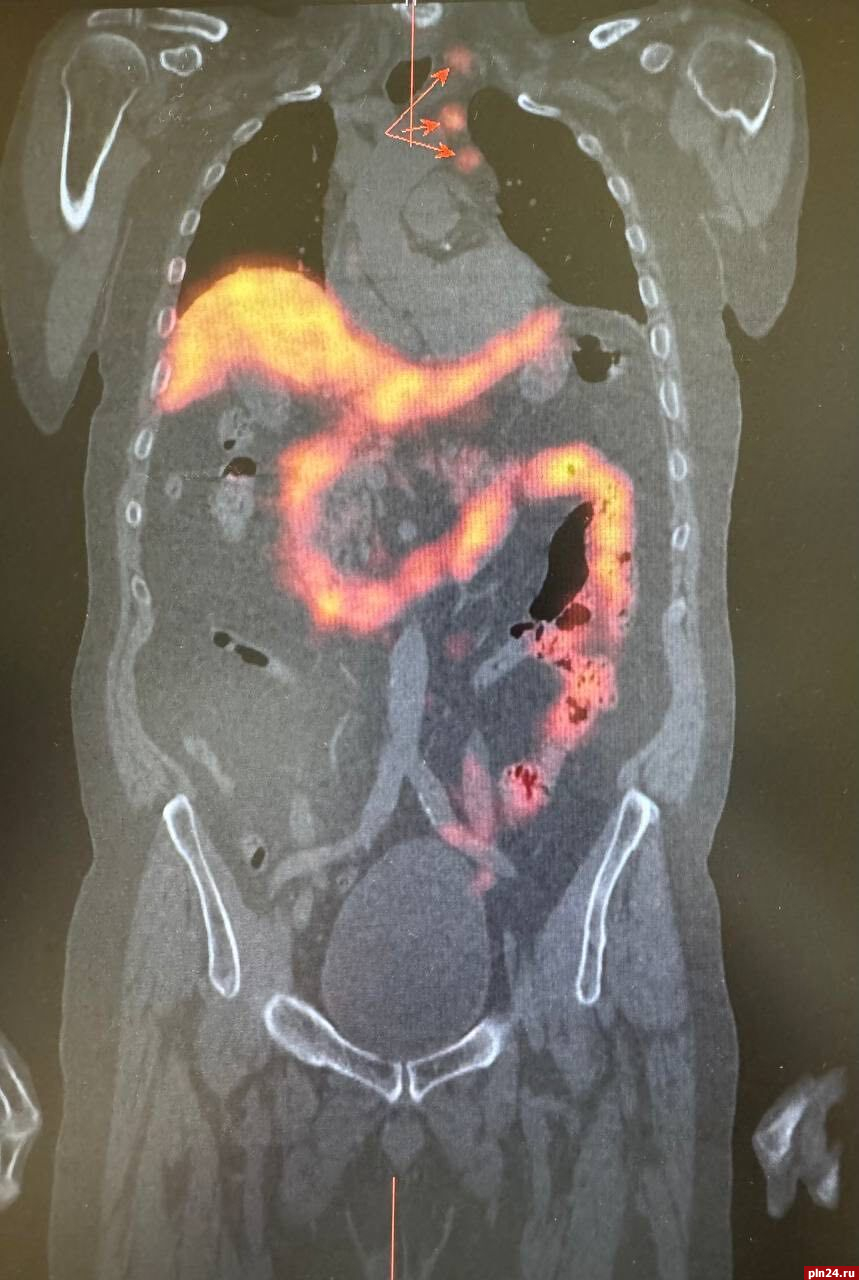

Результаты компьютерной томографии органов грудной клетки выявили наличие внутригрудных лимфатических узлов, которые выглядели подозрительными на предмет метастатического поражения. Однако, кроме этого, значимых вторичных изменений в других органах не обнаружили.

Для уточнения диагноза и получения более детальной информации о состоянии лимфатических узлов была назначена радионуклидная диагностика. Этот метод позволил более точно определить наличие злокачественного опухолевого процесса в предстательной железе, а также подтвердить метастатическое поражение ранее выявленных лимфатических узлов в грудной клетке. Кроме того, радионуклидное исследование показало активное накопление технеция ПСМА в парааортальных лимфатических узлах с обеих сторон.

При этом важно отметить, что на компьютерной томографии не было явных структурных изменений, что затрудняло оценку их состояния и возможности метастазирования, уточнили в министерстве.